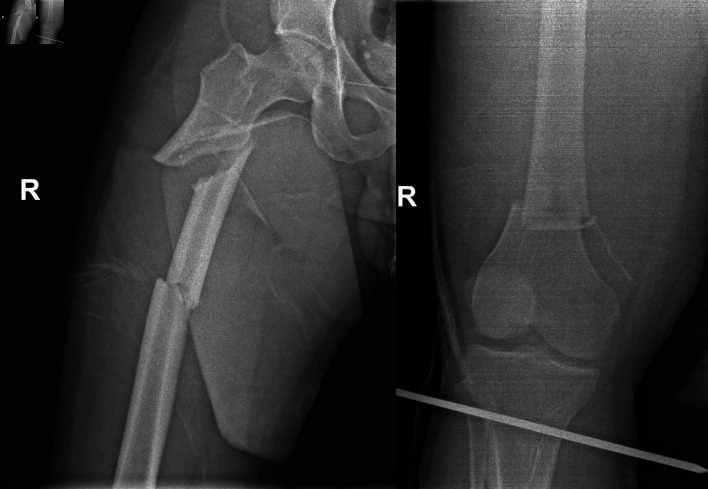

Femoral fractures are indubitably common injuries that can occur either from high-energy trauma in young patients or due to fragility in the geriatric population. Femoral fractures affecting two or more regions of the femur are exceedingly infrequent injuries, ordinarily caused by high-energy trauma and are considered segmental femoral fractures. We present a rare case of a 33-year-old male patient presented to our Emergency Department with multiple femoral fractures at the subtrochanteric, diaphyseal and supracondylar femoral regions, a condition regarded as double segmental femoral fracture. After assiduous consideration of treatment options, intramedullary nailing was employed for osteosynthesis. Fracture reduction was laborious, as an entirely separated femoral fragment was present between the fracture lines. The reaming process required paramount attentiveness as the middle femoral fragment was prone to rotational displacement by the reamer. Finally, the intramedullary nail was successfully placed, and the patient was discharged without complications after 11 days of hospitalization. Currently, the patient is capable of full weight-bearing without crutches. This paper underlines the challenges that double-segmental femoral fractures' treatment can bring on to the orthopedic surgeon.

Abstract Image